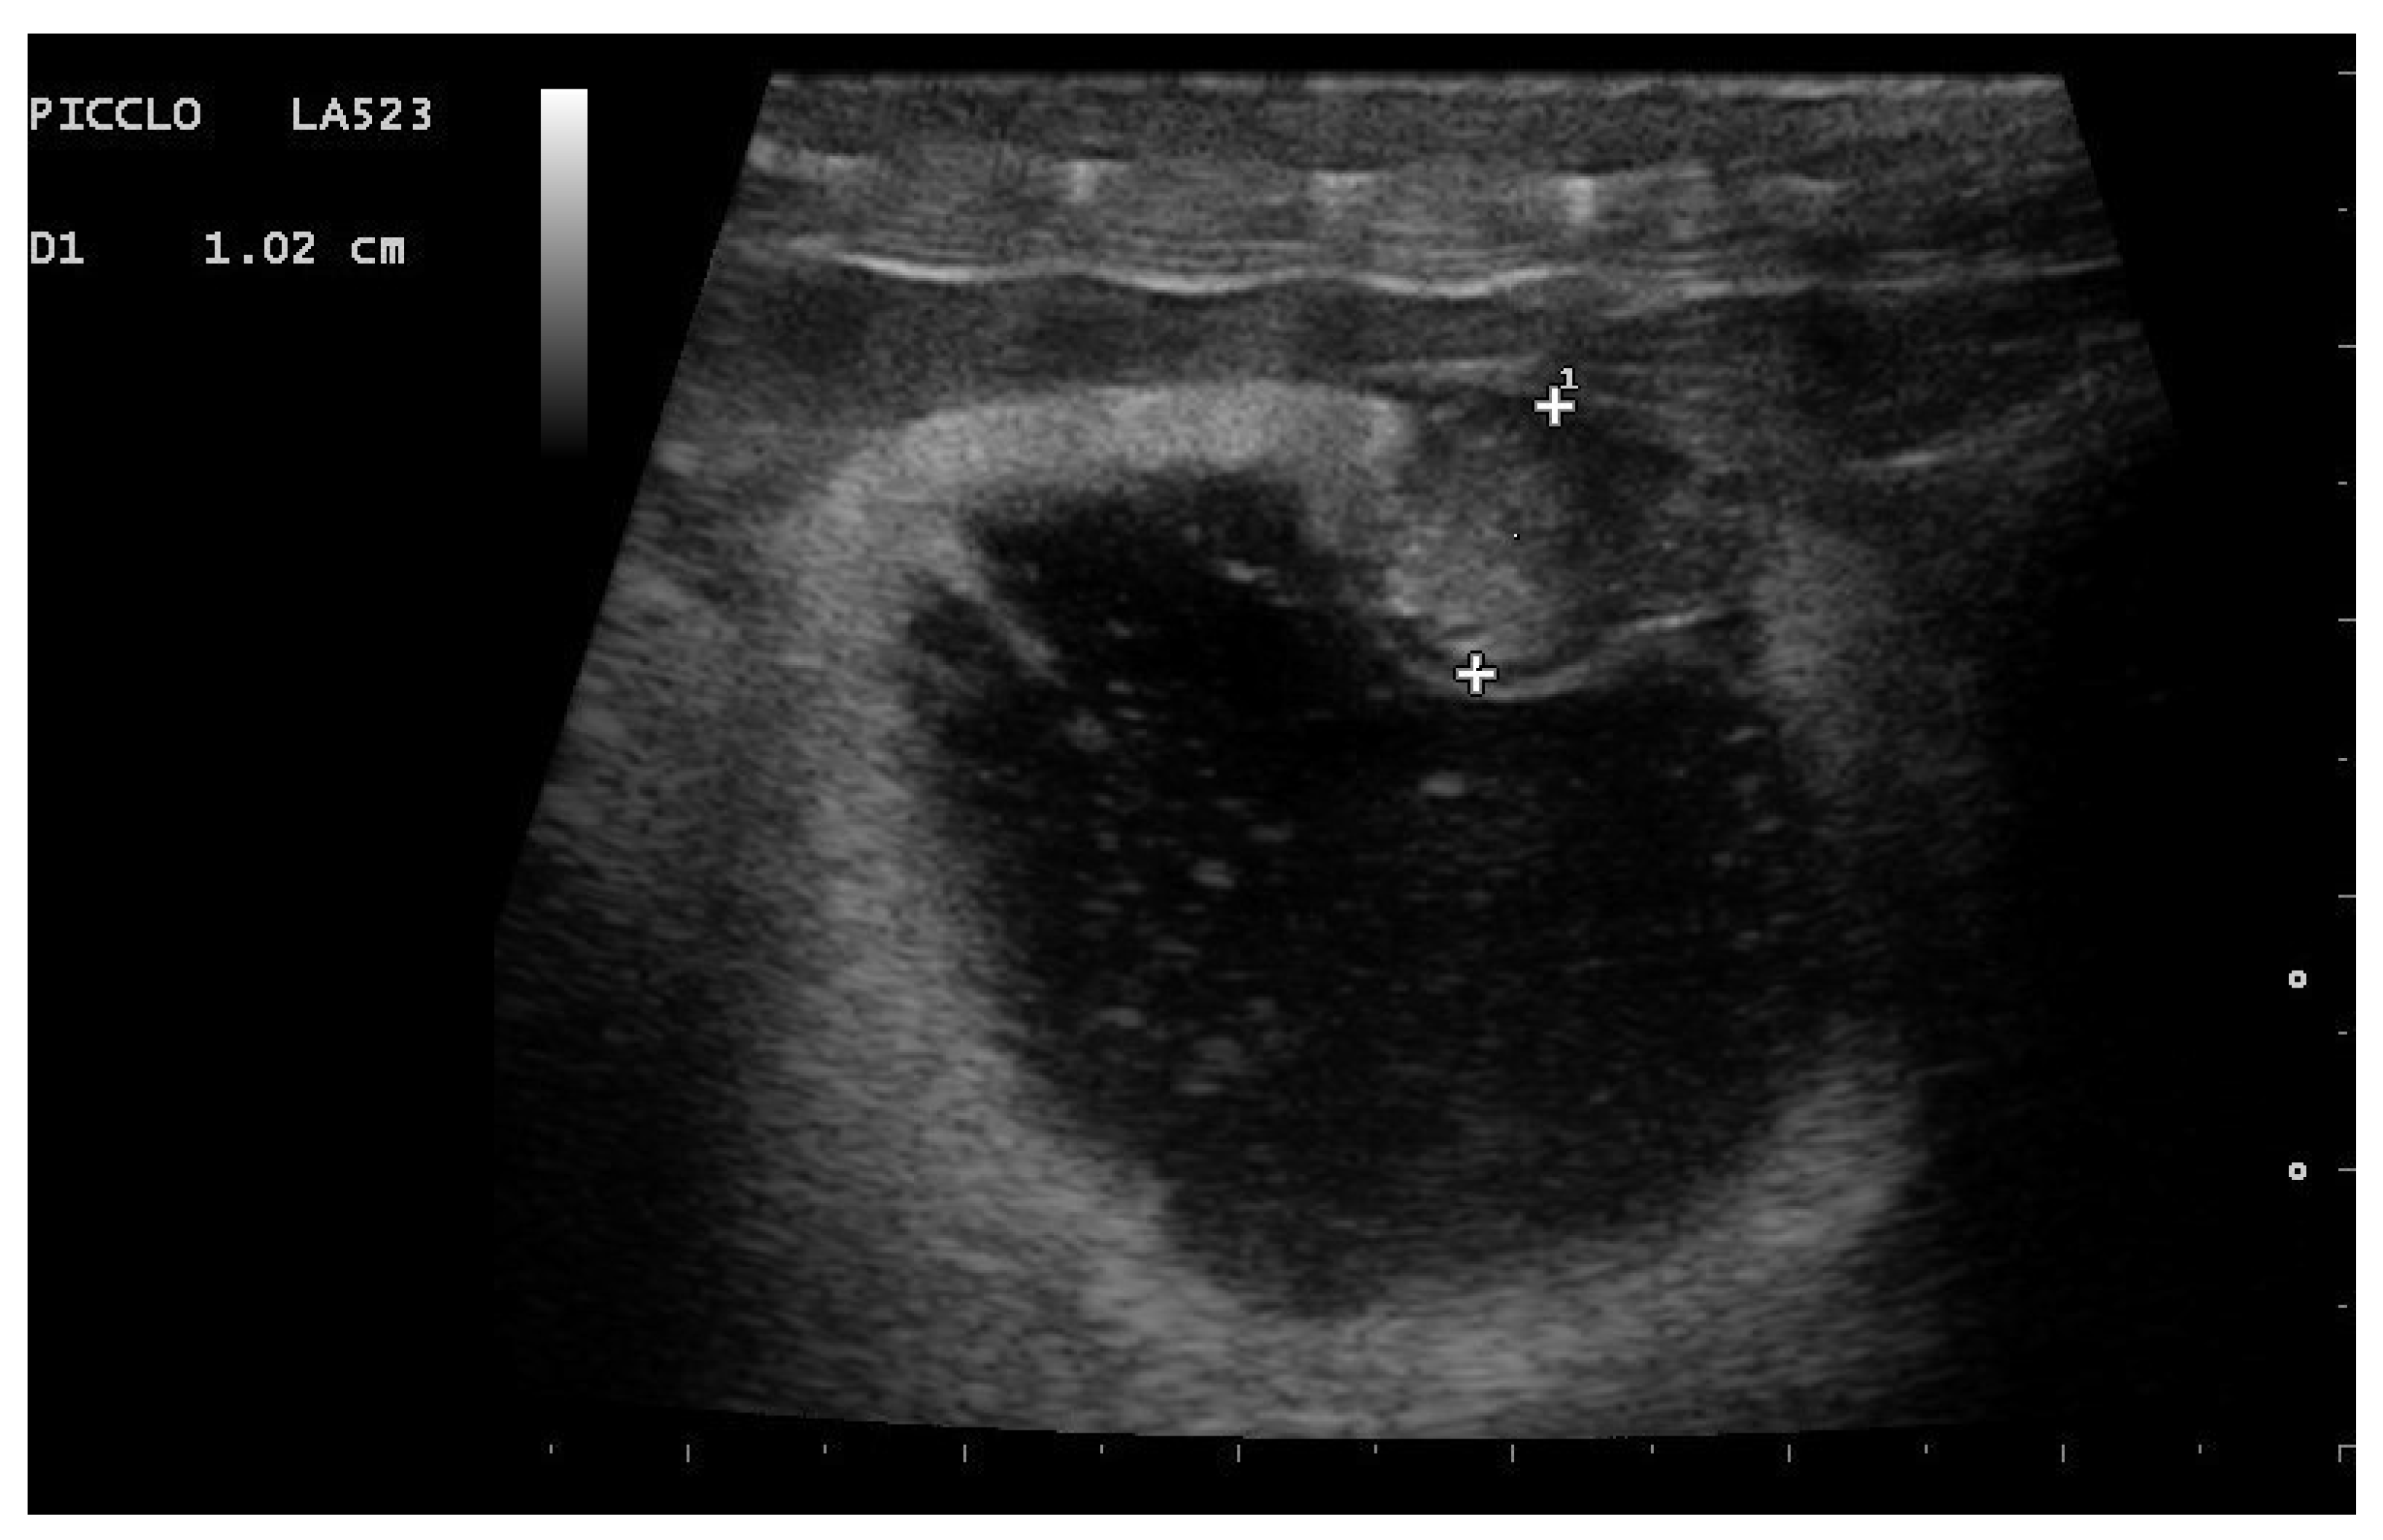

- Garcia, V.C.; Almeida-Santos, S.M. Reproductive cycles of neotropical boid snakes evaluated by ultrasound. Zoo Biol. 2021, 1–10. [Google Scholar] [CrossRef]

- Isaza, R.; Ackerman, N.; Jacobson, E.R. Ultrasound imaging of the coelomic structures in the Boa constrictor (Boa constrictor). Vet. Radiol. Ultrasound 1993, 34, 445–450. [Google Scholar] [CrossRef]